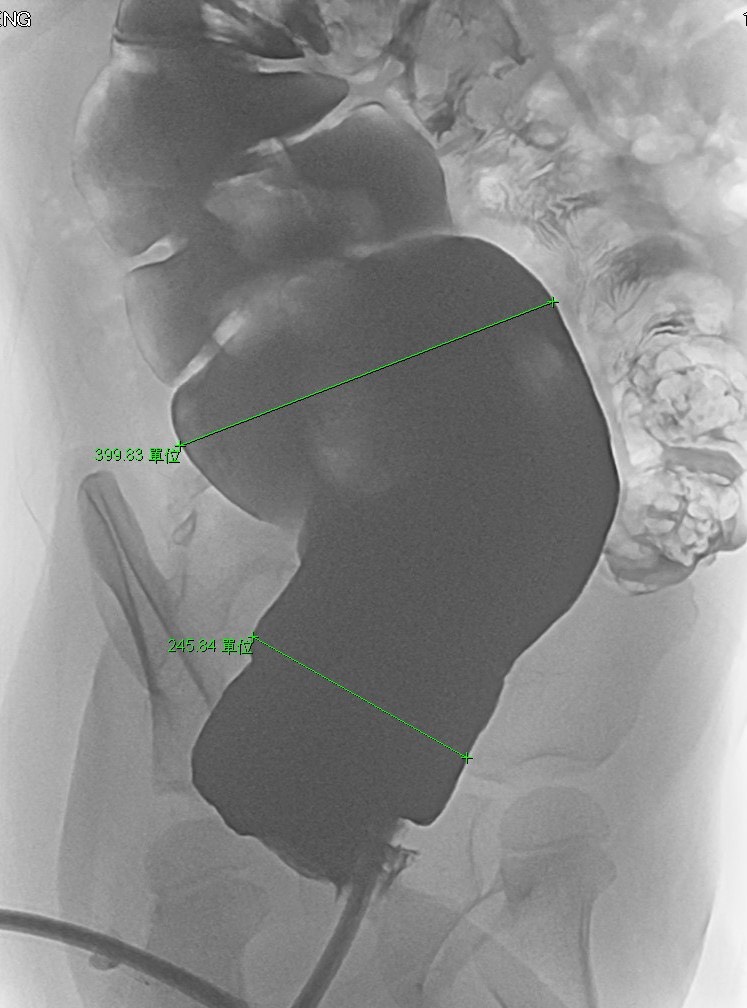

在新營醫院,小兒科張經旼醫師詳細詢問病史,並安排一系列檢查,包括影像學與腸道評估,最終確診為先天性的「巨結腸症」。張經旼醫師指出,巨結腸症是因腸道神經發育異常,導致腸道蠕動不足,糞便無法順利排出,症狀常被誤以為只是單純便秘,因而延誤診斷。